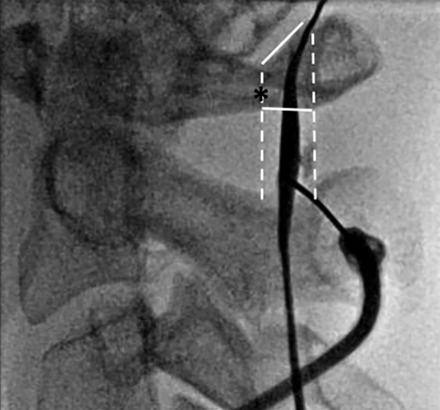

Intraprocedural fluoroscopic image demonstrating proper use of the flare point as an osseous landmark during a C1–2 puncture for a myelogram with the subject supine. The flare point (asterisk) is used to approximate the dorsal border of the spinal cord, and the needle is placed centrally between the dorsal cord border and the spinolaminar line (white dashed lines). Although the most capacious portion of the posterior subarachnoid space is in the mid-C1–2 interspace, successful puncture was performed in the slightly thinner lower portion of the interspace.

Measurements were performed on high-resolution sagittal cervical myelogram CT reformatted images. A line was drawn along the posterior margin of the SC (short dashed white line), with a second line approximating the SL (long dashed white line). The osseous canal was measured along the upper, mid, and lower aspects of the C1–2 interspace (solid lines) from the posterior margin of the dens to the SL. Additional measurements were performed between the posterior cord to the SL and the posterior cord to the posterior dura at the upper, mid, and lower aspects of the C1–2 interspace (not shown).